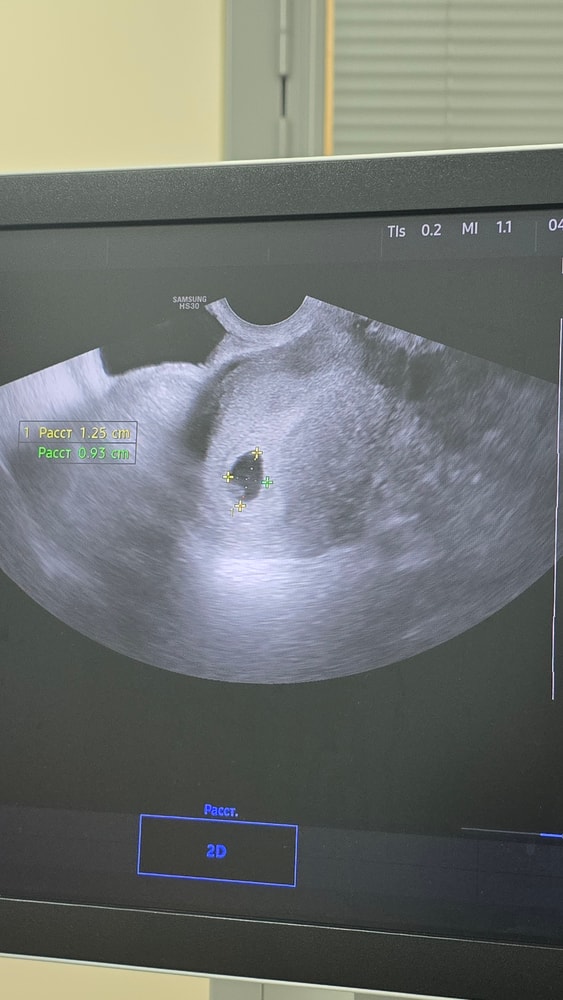

Все что написано на бумажке - беременность маточная, плодное яйцо 10мм, жёлтое тело справа.

Меня больше интересует белый пузырёк внутри плодного яйца. Что это такое? Это желточный мешочек или уже зачатки эмбриона? Или возможно это стадия до бриллиантового колечка или уже после его? Вопросов много, но ответа найти не смогла тут у девочек либо пока пустое плодное яйцо, либо уже колечко, а картинку как у меня найти не смогла

Думаю это жм🤗